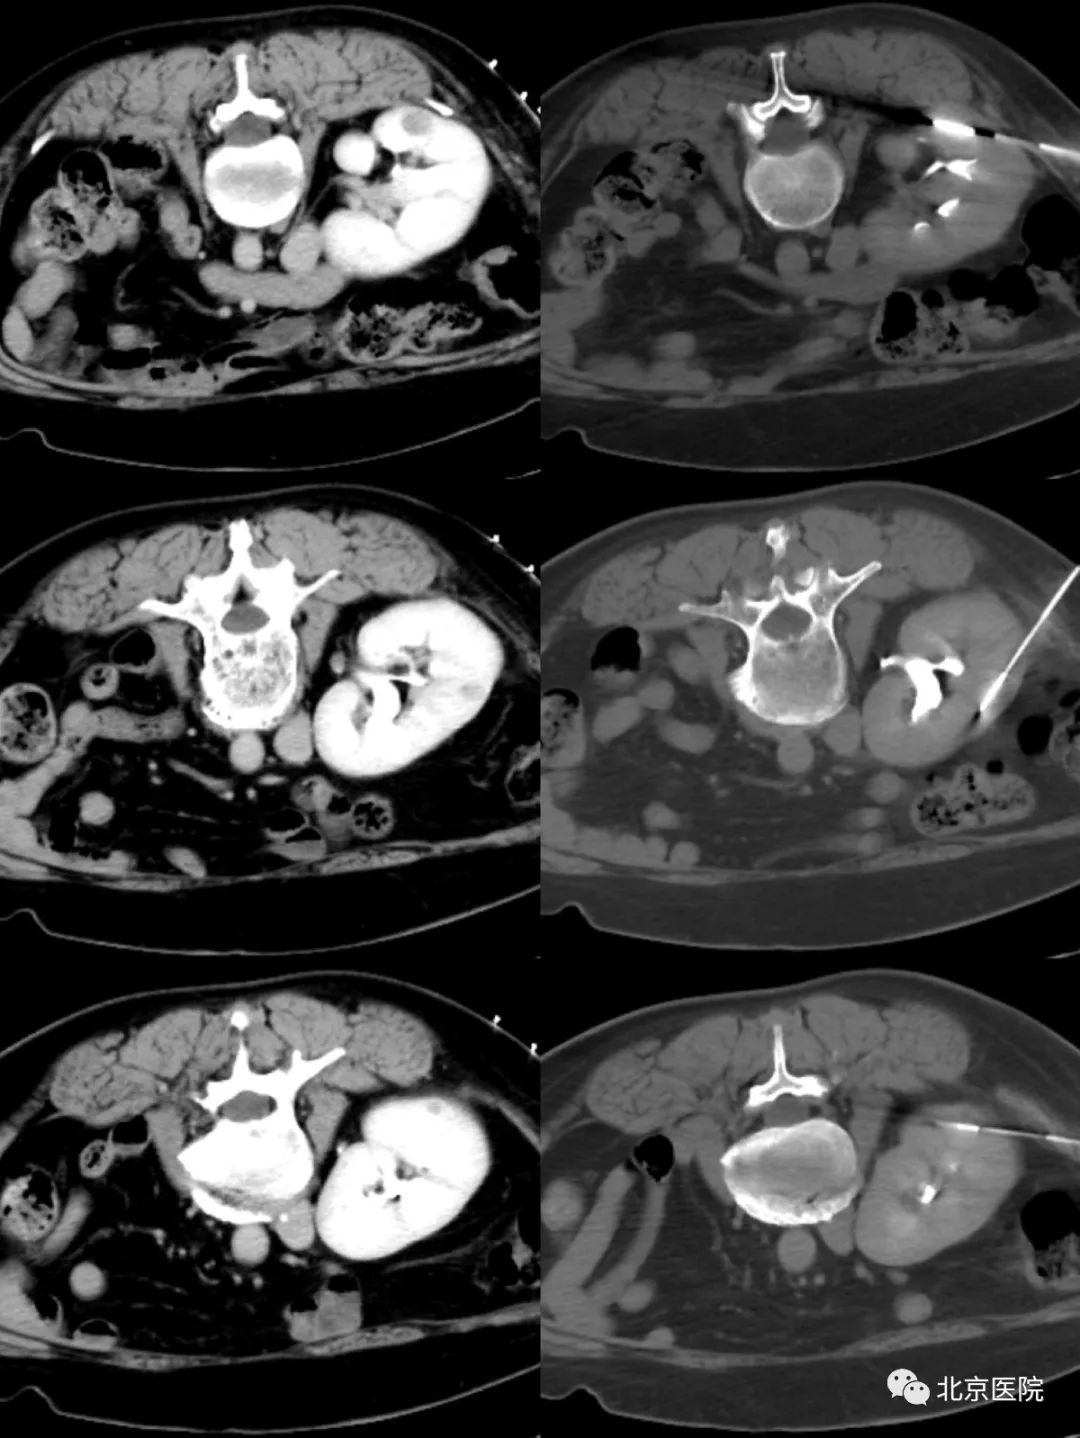

消融后复查增强CT,肿瘤区域呈完全低密度显像,并且无增强

近日,北京医院泌尿外科收治了一名中年女性,6年前因双肾同时发现肾癌,接受了左肾癌根治性切除术、右侧保留肾单位的肾部分切除术,术后规律复查,1月前 CT扫描发现右肾内出现可疑的肿瘤复发,进一步行磁共振检查发现3处可疑病灶,全身其他部位未见转移。考虑患者仅有一个不完整的肾,又复发了多个小的肾肿瘤,目前肾功能正常,若行根治性肾切除,则必然需要长期透析治疗,严重影响生活质量;若再次行肾肿瘤部分切除术,因为手术区域粘连,同时仅一处复发灶外凸明显,另两处病灶B超定位困难,手术难度极大,难以保证彻底消灭肿瘤。北京医院肿瘤微创治疗中心李晓光主任团队借助CT引导下精准定位技术,对这三处病灶实施一次性经皮穿刺活检同步微波消融治疗。患者仅需俯卧在CT检查床上保持不动,局部麻醉、只有几个穿刺针眼、不到一个小时就达到了彻底灭活3个肿瘤的目的。整个治疗过程中患者没有不适感觉,与医生自如交流,术后第二天,患者即顺利出院。